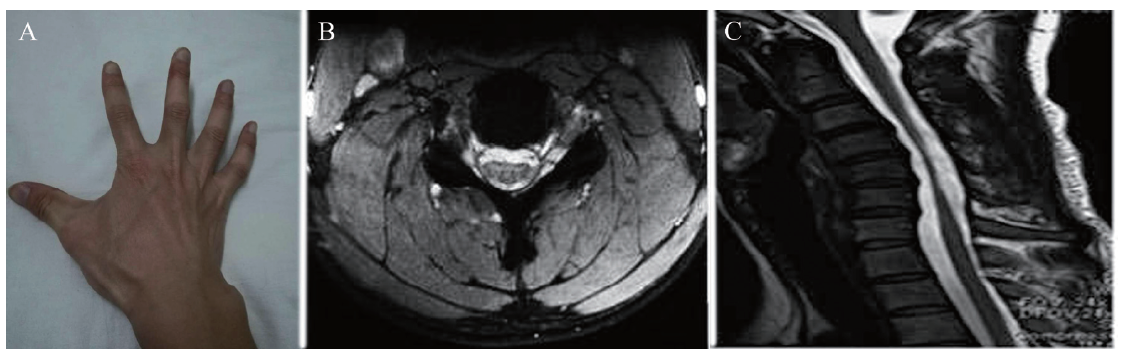

例 2,患者男,17岁,高中学生,河北邯郸人,现居地为河北省邯郸市,因“右手无力,右手小拇指不能完全伸直,且伸直时可出现震颤”于2009年4月16日入我院。患者无烟酒等不良嗜好。无传染病史和手术外伤史。父亲患有高血压病10年,母亲患有2型糖尿病,妹妹身体状况良好,家族成员中未发现遗传病及传染病。体格检查:神志清晰,语言流利,颅神经检查正常,锥体束征阴性。右手骨间肌、大小鱼际肌明显萎缩,可见肌束颤动。右侧前臂桡侧屈肌明显受累,呈斜坡状改变。双侧上肢肌力、肌张力和感觉正常。双侧肘关节、肩关节活动正常。双侧下肢肌力、肌张力和感觉正常,膝踝反射对称活跃,脊柱无畸形,无扣压痛。实验室检查:CPK、乳酸脱氢酶、血肌酸正常,脑电图、脑脊液常规正常。颈椎过屈位MRI显示低位脊髓硬脊膜前移,颈6 ~ 胸2水平脊髓受压变扁,硬膜外腔呈新月状增宽。肌电图显示神经源性损害,神经传导速度大致正常。双下肢肌电图正常。诊断为平山病。给予口服维生素B、肌苷及佩戴颈托治疗后于2009年5月7日出院。随访5年,病情好转,手无力和肌萎缩无明显加重。